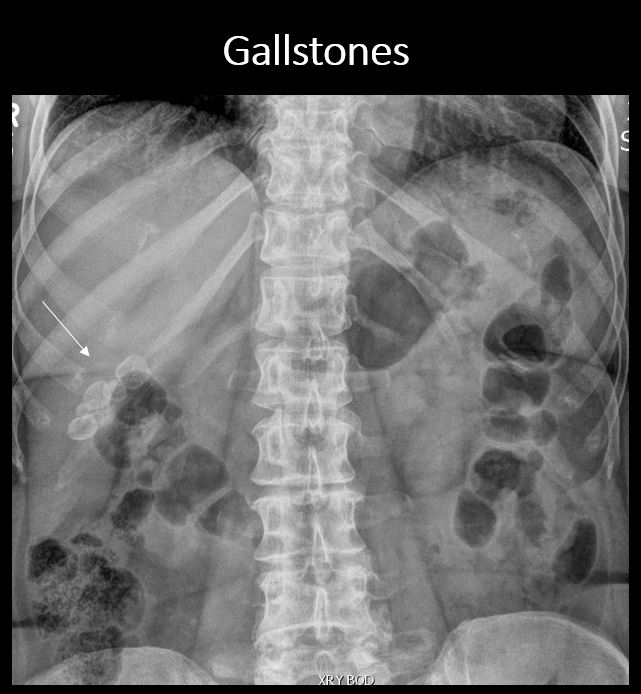

There is calcification in the expected region of the gallbladder. |

No | NA |